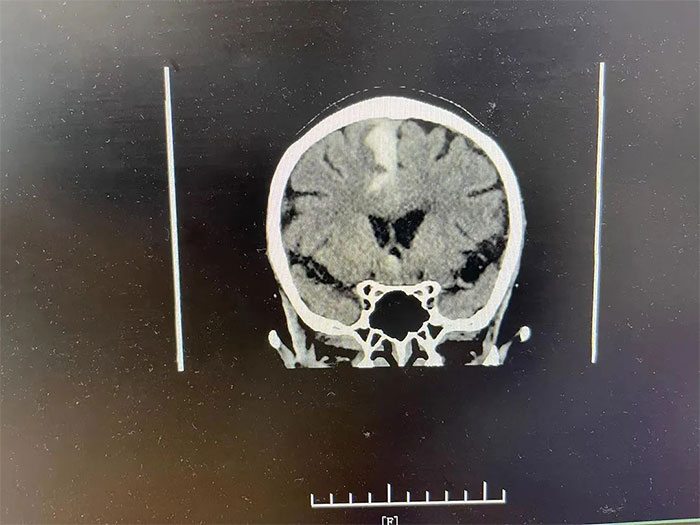

▲ 通过治疗,出血已基本吸收